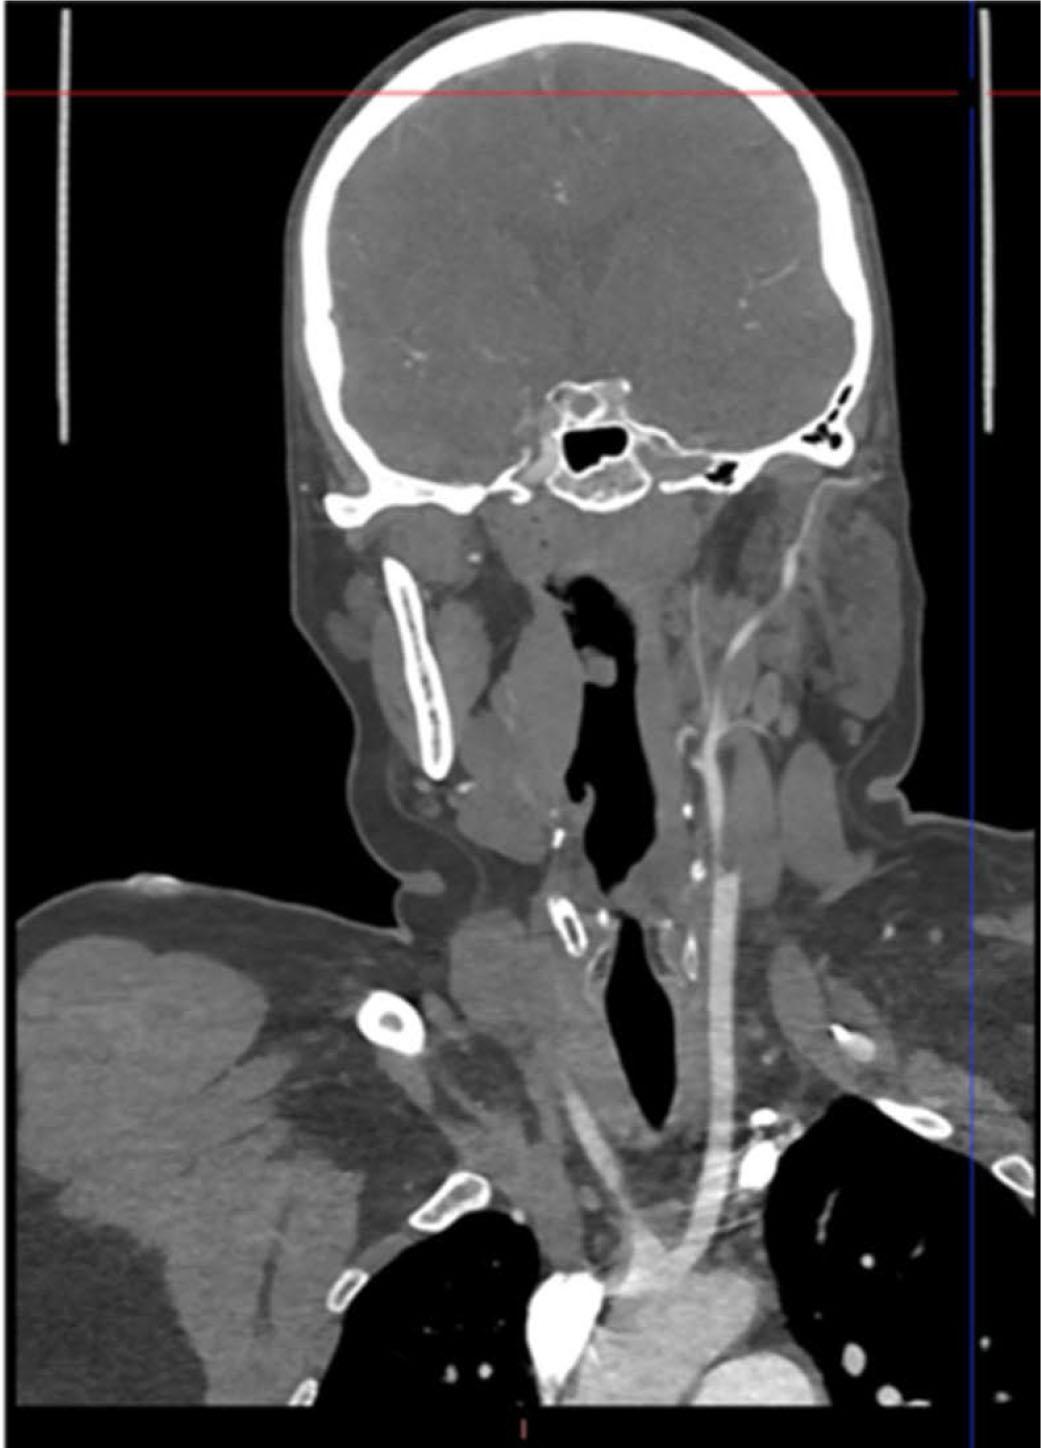

On the fourth day of hospitalization, the patient experienced sudden neurological deterioration. Emergency echocardiography indicated embolization of the thrombus from the left ventricular apex. Cerebral CT angiography revealed an acute thrombotic occlusion of the left internal carotid artery. In accordance with the European Stroke Organization guidelines for patients with acute ischemic stroke caused by large vessel occlusion within 6 hours of symptom onset, emergency thrombectomy was performed, resulting in successful extraction of the thrombotic material (Figure 4 A,B). A native CT scan performed 24 hours post-intervention showed no evidence of cerebral ischemic lesions (Figure 5). Echocardiography confirmed the absence of the apical thrombus in the left ventricle.

CT scan performed 24 hours post thrombectomy showing no evidence of cerebral ischemic lesions